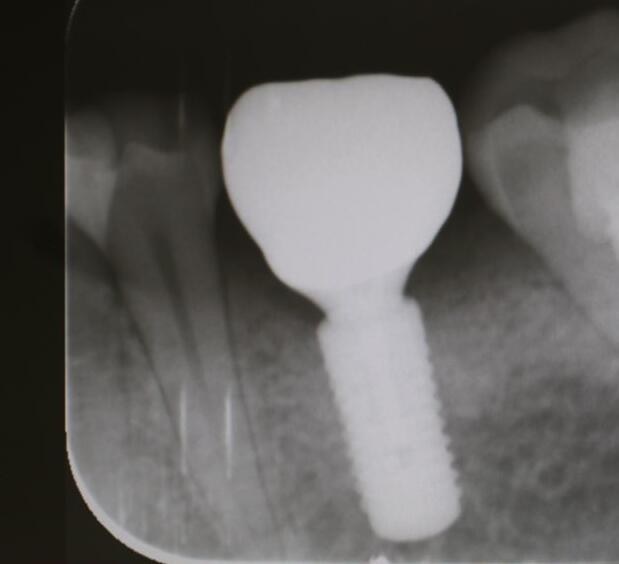

牙齒種植是指在牙槽骨內(nèi)植入人工牙根,待人工牙根成活之后,就能夠在其上連接入基臺(tái)和義齒。能夠仿真牙的果,并且其療也是理想的,因此很多人都稱他為人類的第3副牙齒 。種植牙的維持時(shí)間一般在10-20年左右,果好。